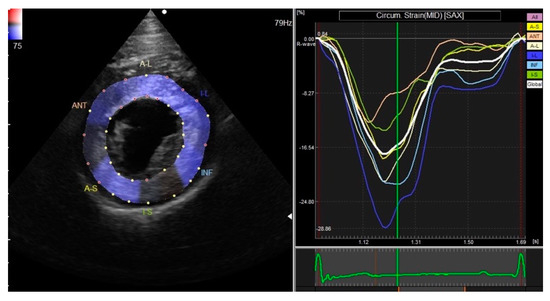

3.2. Two-Dimensional Speckle-Tracking Echocardiography

| GRS | 39.46 ± 12.46 | 37.93 | 34.63–44.29 | 19.46–66.46 |

| GCS | −12.99 ± 2.46 | −12.92 | −13.94–−12.04 | −19.40–−9.32 |

| STI | 65.74 ± 24.78 | 62.20 | 56.13–75.35 | 24.58–119.00 |